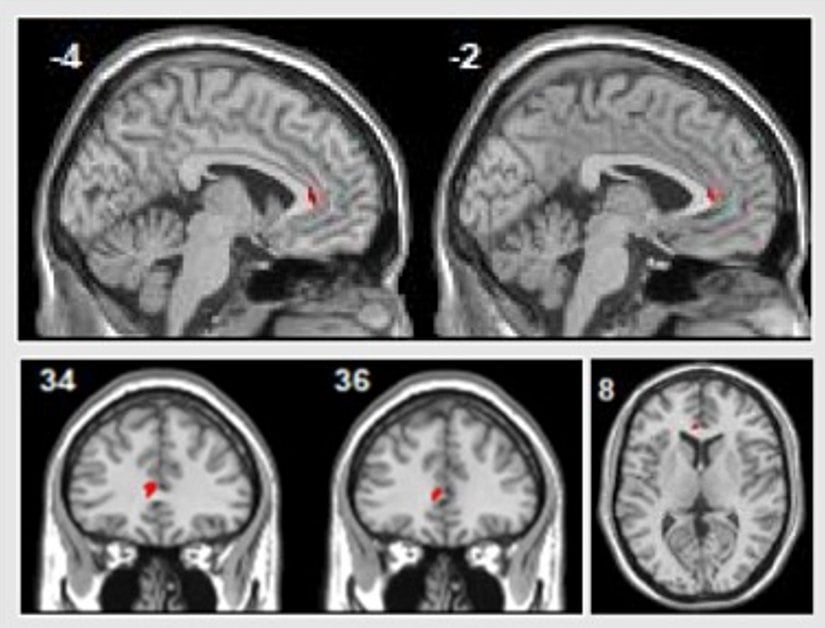

Bir başka bulgu bilişsel davranış terapisi ve psikodinamik terapi sonrasında hastaların sol rostral ön singulat alanlarındaki aktivite artışını gösteriyor (yukarıdaki görsele bakınız; sağlıklı kontrol gruplarının bu değişimi göstermemesi bulgunun sadece görüntü izleme görevlerindeki geçen zaman ya da pratik yapma etkisine bağlı olmadığını belirtiyor). Bu beyin bölgesi, amigdala aktivitesini baskılamak gibi etkilerle, çekirdek duygu işlemlerini gerçekleştiren bölgelerle güçlü şekilde bağlantılıdır. Daha önceki kanıtlar ön singulat ve amigdala arasındaki bağlantıların majör depresyonda daha zayıf olduğunu gösteriyor.

Bu durum majör depresyon hastalarında duyguların neden daha yoğun bir şekilde hissedildiğini açıklıyor. Yani öyle gözüküyor ki psikoterapinin etkilerinden biri de bu zarar görmüş bağlantının yeniden inşası olabilir. Meta-analiz bize bu inşanın nasıl gerçekleştiğini kesin olarak gösteremese de ihtimallerden biri “bilişsel yeniden değerlendirme” gibi yöntemlerle zorlu deneyimleri yorumlamanın yeni yollarını bulmak olabilir.